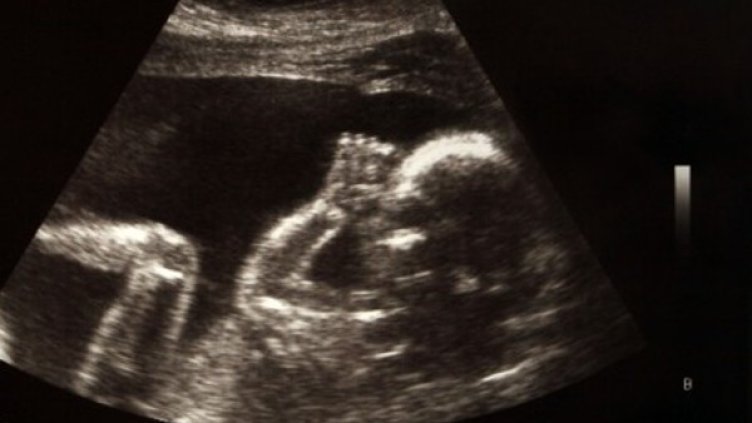

Родителите вече могат да гушкат бебетата си още преди да са се родили, като получат 3-D отпечатък от снимката им, направена в утробата на майката, пише в. "Дейли мирър", цитиран от БТА.

Услугата струва 150 британски лири. Получената скулптурка на нероденото дете може да се сложи също на поставка или в рамка. Клиентките трябва да изпратят снимка от видеозон на зародиша в напреднала фаза. Фотографията се транспонира в 3D формат, след което се предоставя на триизмерен принтер, който изготвя точното копие на бебето от утробата.